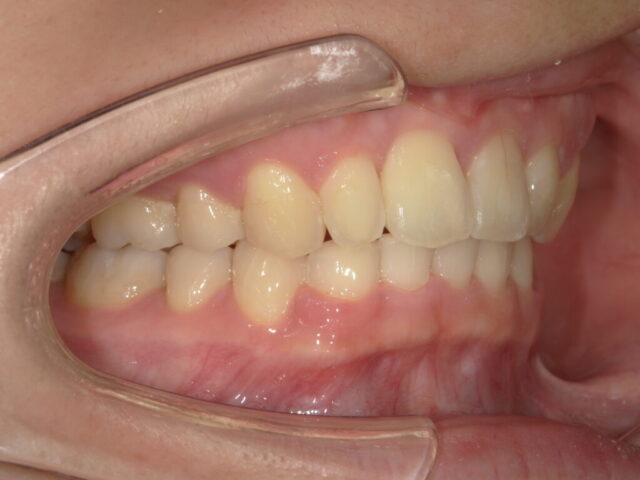

過蓋咬合(深い噛み合わせ)の改善

成人矯正

| 診断名 | 過蓋咬合 / 下顎前歯の先天欠如 |

| 治療期間・回数 | 2年5ヵ月 |

| 治療方法 | ワイヤー矯正(上顎4番 抜歯) |

| 費用 | 825,000円(税込) |

| デメリット・注意点 | 治療初期は痛みが生じる場合がありますが、約1週間で慣れていただけます。 |